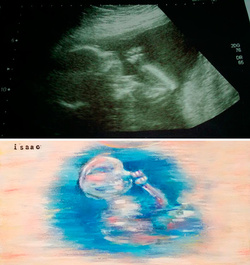

„Ecografiile îmi tot arătau că bebele este bine, în ciuda faptului că nu îi simţeam mişcările. Cu toate acestea, deşi cu un rezultat bun, ecografiile gri mi se păreau fade, fără personalitate”, povesteşte Laura despre momentul în care s-a născut ideea fascinantă.

Imaginile ei au devenit în scurt timp populare, astfel că tot mai multe mămici au rugat-o să le picteze şi lor ecografiile, contra unei sume de bani. Acum, Laura a renunţat la meseria ei de avocat şi pictează ecografii.

Operele de artă ale Laurei celebrează sarcina şi naşterea, frumuseţea vieţii încă nenăscute. Cu toate că picturile sunt fascinante, artista este de părere că subiectul lor este cel care creează, în fapt, magia.